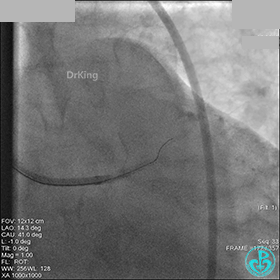

先处理前降支开口严重狭窄并顺利植入前降支到左主干支架。

没有说明是否进行了右冠脉介入治疗。